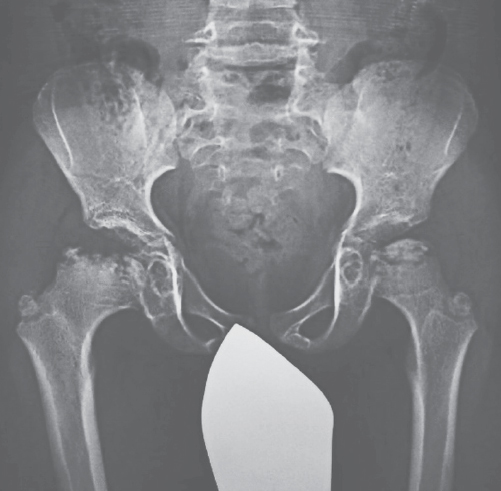

Форма В МПС II в большей степени похожа на синдром Шейе. Заболевание диагностируют, обычно, в конце первого или на втором десятилетии жизни. Рано формируются паховые и пупочные грыжи, поражение сердечно-сосудистой системы, происходят лицевые изменения по типу «гаргоилизма», появляются признаки множественного дизостоза (рис. 4), тугоподвижность суставов (рис. 5), нейросенсорная тугоухость, ретинопатия, возможна обструкция дыхательных путей, ночные апноэ, карпальный туннельный синдром [9]. Течение заболевания медленно прогрессирующее. Продолжительность жизни варьирует в широком диапазоне. Одно из типичных осложнений у пациентов старшего возраста — сужение просвета трахеи, приводящее к необходимости стентирования и/или трахеостомии. Наиболее частой причиной ранней гибели больных на втором или третьем десятилетии жизни становится дыхательная или сердечная недостаточность. Иногда больные доживают до старческого возраста.

Рис. 5. Диспластические и дистрофические изменения тазобедренных суставов при мукополисахаридозе типа II

Fig. 5. Hip changes in MPS II patients